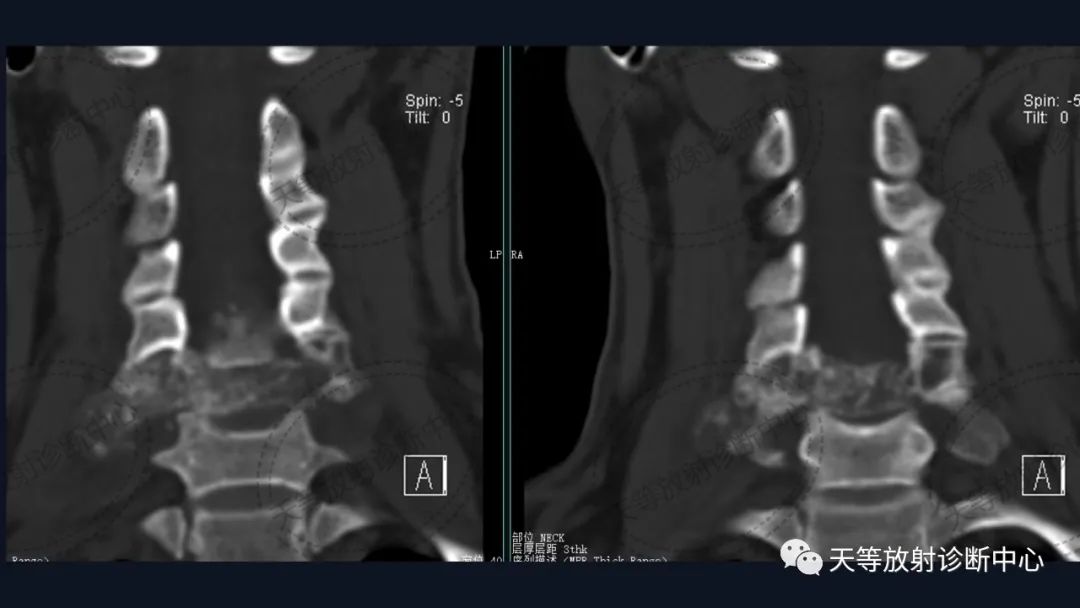

术后内固定支架

外生性生长+椎旁软组织肿块+骨破坏并骨钙化。

1)骨破坏累及椎体及附件,外生性生长,形式为溶骨性骨破坏、骨质侵蚀,明显侵袭性;

2)破坏区伴有钙化,不定型,表现为泥沙样、斑点状、点状或条状等。

术后容易复发。